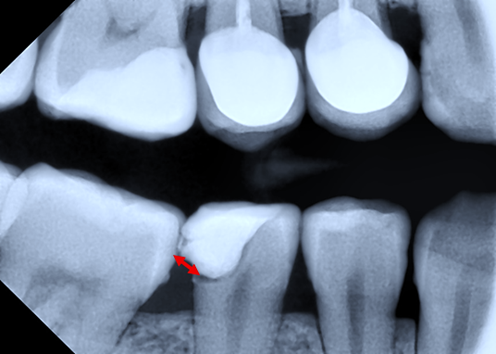

The proximal morphology of the restorations was evaluated by assessing the emergence profile categorized as concave, convex, or straight surface. Similarly, the cervical marginal adaptation of the restoration was studied by evaluating the presence of a harmonious transition between tooth and restoration or a visible radiographic overhang (Fig. 1), with the calculation of its size.

|

Fig. 1 Bitewing radiography. Distal restoration in tooth 45 with the presence of overhang. Note: Red line – overhang. |